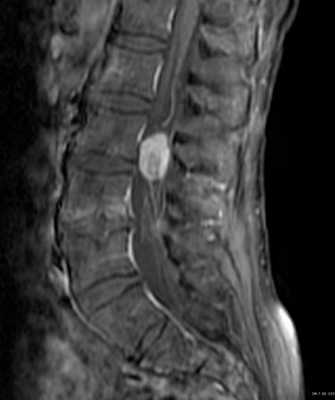

Локальная киста обычно наблюдается в месте наибольшего сдавления спинного мозга кистой или грыжей диска. Чаще они наблюдаются при травмах шейного отдела позвоночника. Киста при МРТ позвоночника имеет типичный ликворный сигнал в спинном мозге и может быть окружена зоной миеломаляции.

МРТ шейного отдела позвоночника. Локальная киста. Т2-взвешенная сагиттальная МРТ.

Сирингомиелитические кисты как отдалённое последствие спинальной травмы встречаются у 3-4% пациентов с неврологическими нарушениями. В целом, они относятся к отдалённым последствиям трамы, хотя известны случаи раннего формирования сирингомиелитических кист. Чаще кисты выявляются при МРТ грудном отделе спинного мозга. Замечена связь сирингомиелитических кист с деформацией позвоночного канала и посттравматическим его стенозом. В отличие от истинной сирингомиелии они развиваются на фоне атрофии и обычно не сопровождаются вздутием спинного мозга. Кисты наблюдаются с одинаковой частотой как выше, так и ниже уровня травмы. Протяжённость кисты может быть любой. Содержимое кисты обычно ликворное, но бывает и с примесью белка, что повышает сигнал от её содержимого на Т1-зависимых МРТ. На Т2-зависимых МРТ в кисте могут быть зоны потери сигнала, что отражает повышенное давление внутри неё. Отмечено, что дренаж кист в этих случаях наиболее эффективен. Изредка при МРТ в кистах встречаются перегородки.

МРТ шейного отдела позвоночника. Кистозно-атрофические изменения. Т2-взвешенная сагиттальная МРТ.